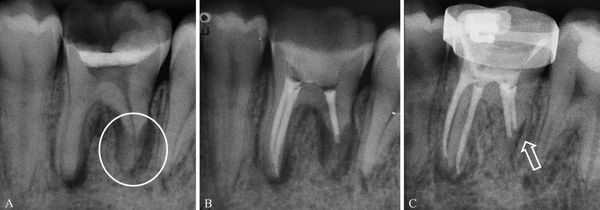

- Поперечные. Линия разлома проходит параллельно жевательной поверхности. На рентгенограмме удается рассмотреть 1-2 полоски просветления, соответствующие уровню повреждения.

При косых медио-дистальных переломах корня зуба, а также в случае, когда линии перелома перпендикулярны рентгеновскому лучу, обнаружить разлом корня с помощью прицельной рентгенологической диагностики довольно сложно. Для уточнения характера патологии проводят КТ. При горизонтальных, вертикальных вестибуло-оральных переломах корня зуба на рентгенограммах выявляют расширение периодонтальной щели. Зона разрежения костной ткани в виде тонкой полоски просветления проходит в участке повреждения. При позднем обращении пациентов рентгенографически в проекции перелома корня зуба определяют участок деструкции кости с нечеткими контурами, наблюдаются признаки резорбции корня. Прицельную рентгенографию проводят дважды: в момент травмы и через неделю.

Слизистая оболочка в области зуба 1.6 физиологической окраски, безболезненная при пальпации. Сам зуб находится под пломбой, занимающей более 2/3 коронки. На нёбной поверхности зуба виден дефект, широко сообщающийся с полостью зуба, при его зондировании возникает боль. В области дефекта есть пародонтальный карман (пространство между десной и зубным корнем) более 4 мм. Определяется поперечная линия перелома нёбного корня ниже уровня десны на 3 мм. Сам нёбный корень в лунке подвижен, при этом щёчные корни остаются неподвижными. Перкуссия (постукивание) зуба 1.6 болезненная. Противоположный жевательный зуб 4.6 находится под металлической коронкой. Пациент направлен на прицельный внутриротовой рентгеновский снимок зуба. Из-за особенностей прицельной рентгенограммы, наложения структур друг на друга и наличия снимка только в одной проекции линия перелома нёбного корня зуба 1.6 определяется недостаточно чётко. Но в связи с наличием явных клинических признаков, указывающих на перелом корня зуба, принято решение о его удалении.